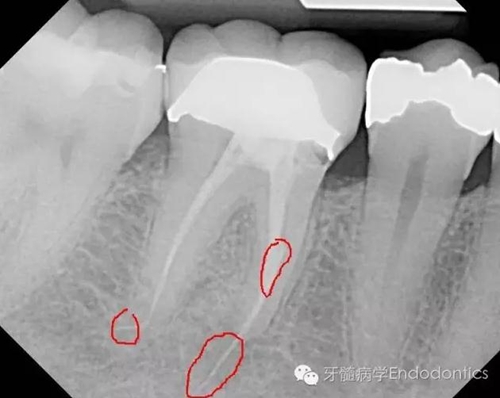

患者因右下第一前磨牙劇烈疼痛、腫脹來(lái)診,自訴2年前該牙行根管治療,突發(fā)劇痛。X線示患牙已行根管治療并超填。患牙診斷為已行根管治療合并急性根尖周膿腫。一些牙醫(yī)和牙髓病專科可能會(huì)直接采取根尖手術(shù)治療患牙,而我認(rèn)為手術(shù)是最終手段,尤其對(duì)于該病例。

圖1.術(shù)前X線片(a)